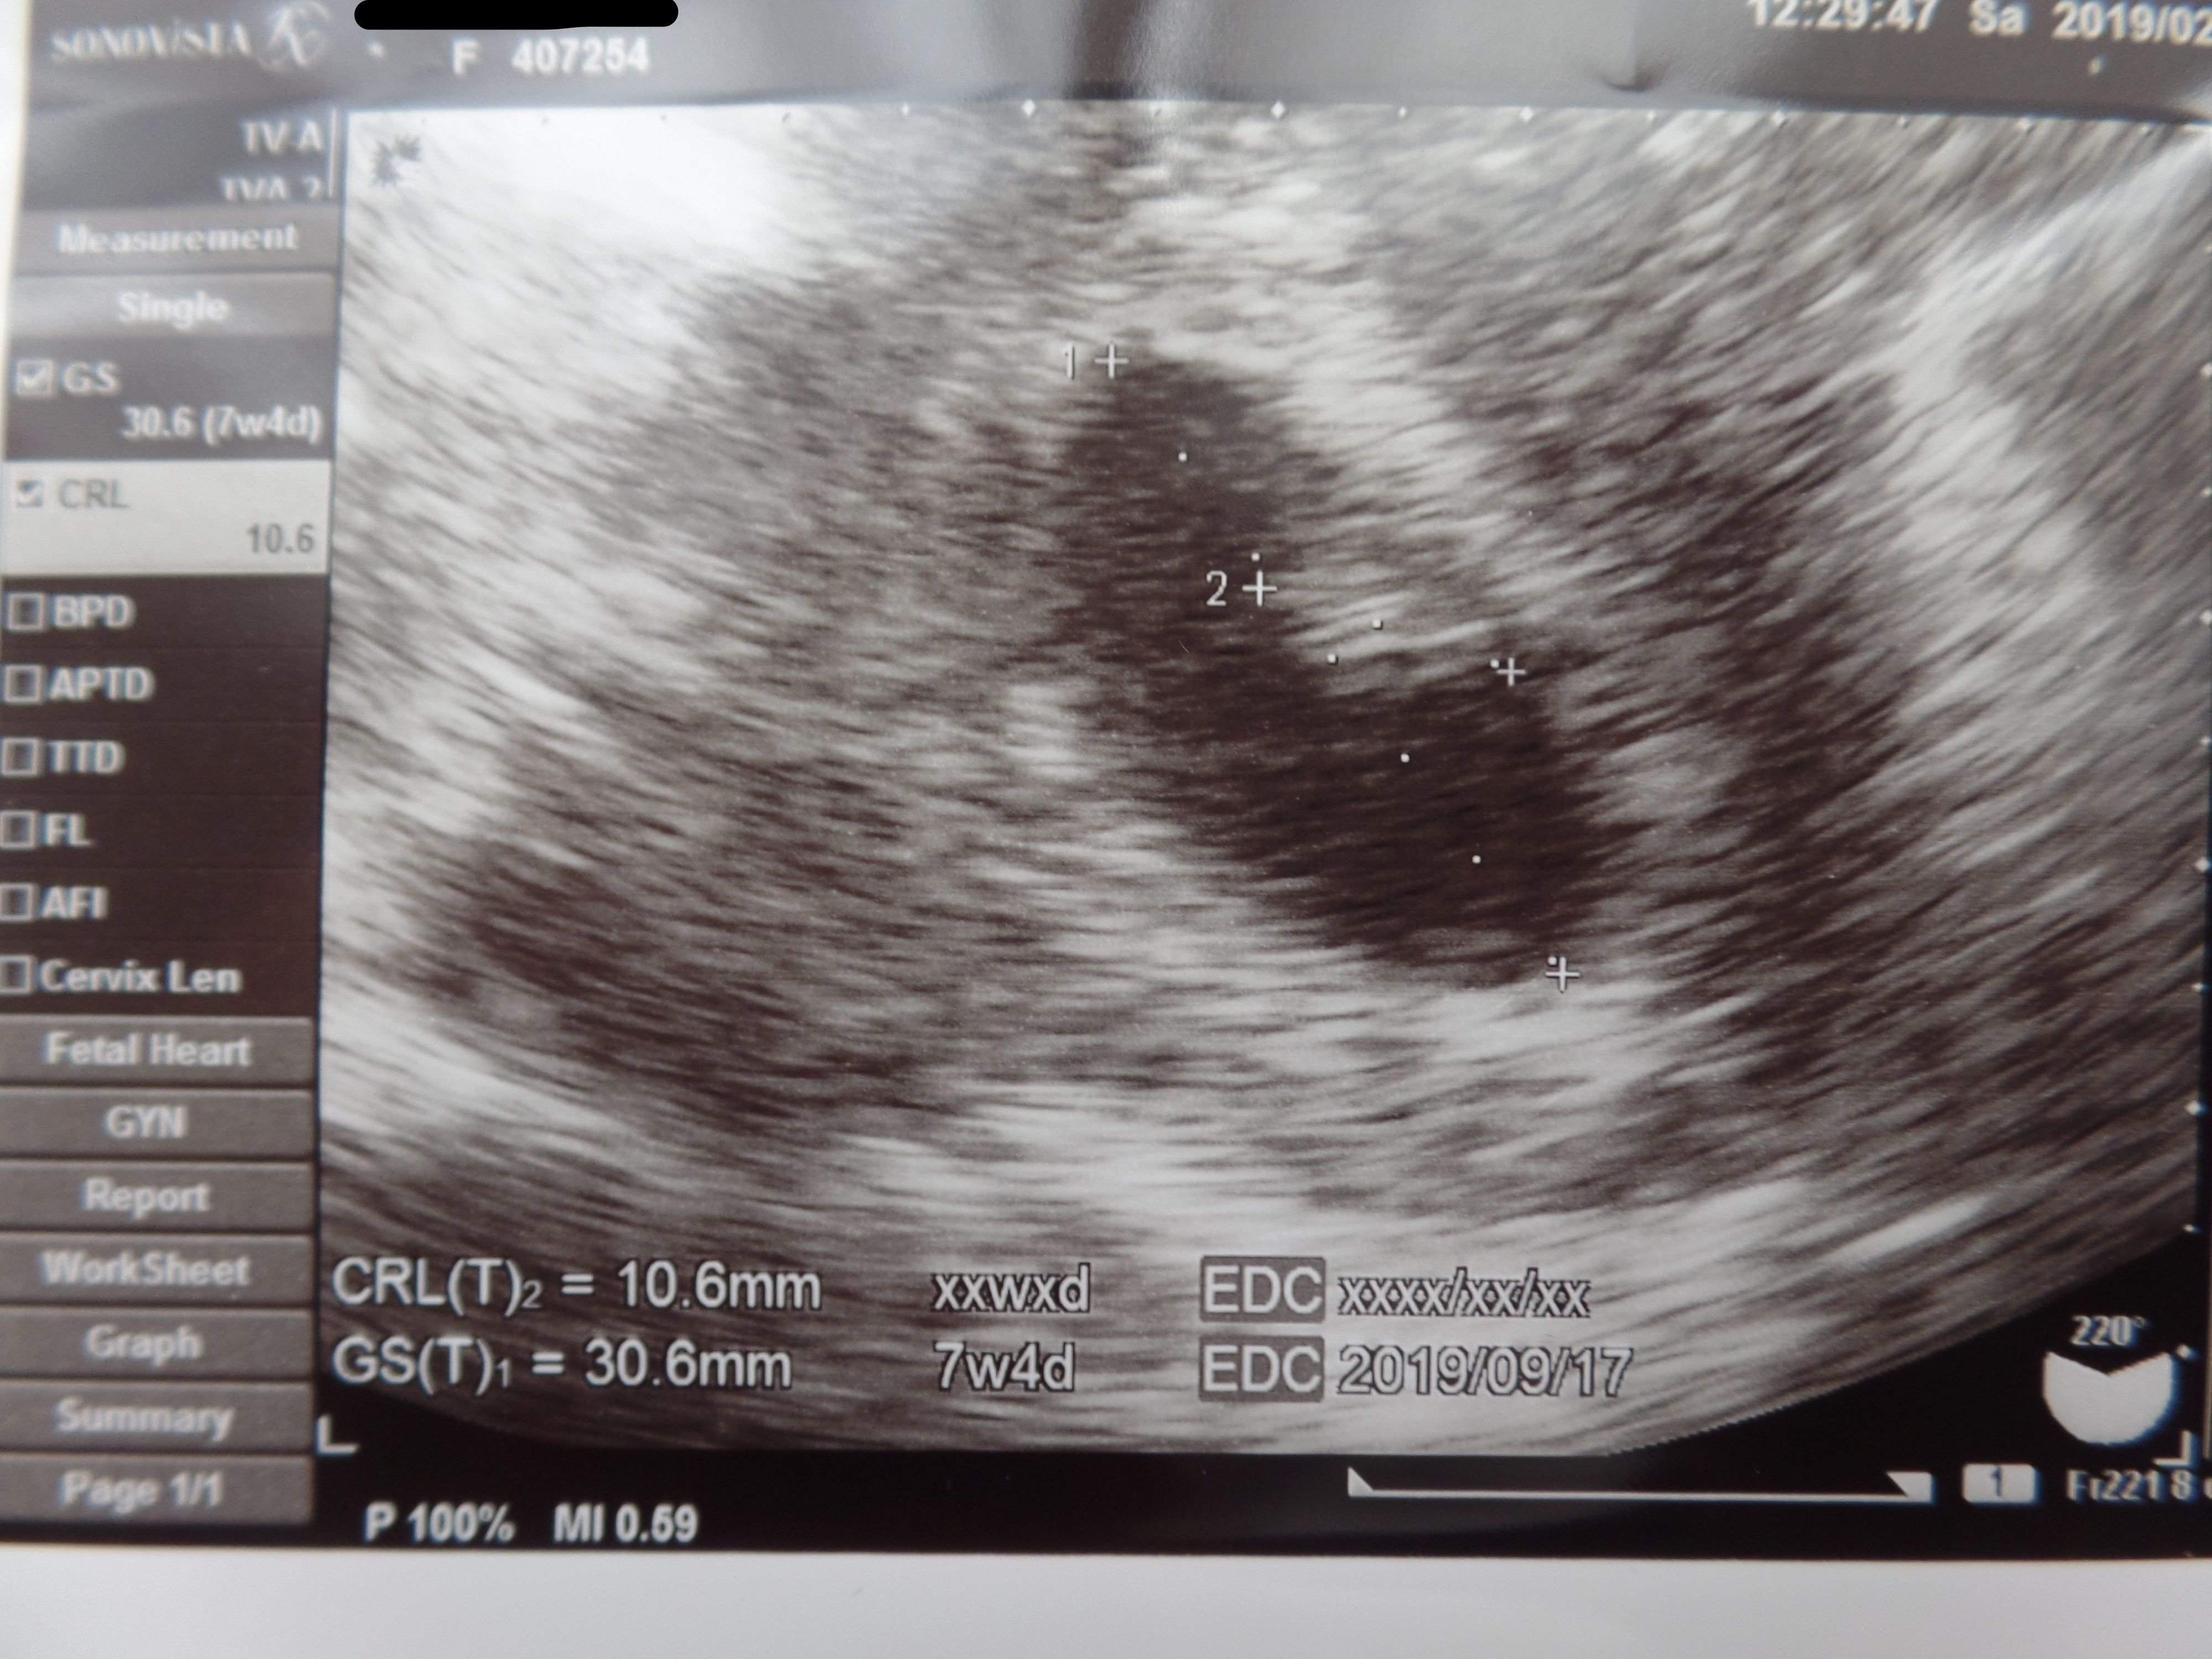

3. 多嚢胞性卵巣症候群(PCOS)から不妊治療を経て高齢出産! エコー写真で喜びを振り返る